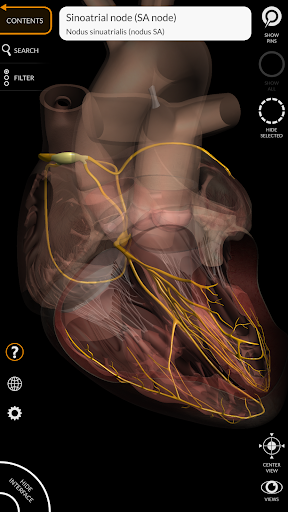

يتيح لك "Anatomy 3D Atlas" دراسة التشريح البشري بطريقة سهلة وتفاعلية.

من خلال واجهة بسيطة وبديهية، من الممكن ملاحظة كل بنية تشريحية من أي زاوية.

تتميز النماذج التشريحية ثلاثية الأبعاد بتفاصيل خاصة ودقة تصل إلى 4K.

نماذج تشريحية ثلاثية الأبعاد

• الجهاز القلبي الوعائي

• الجهاز العصبي

• تدوير وتكبير كل نموذج في مساحة ثلاثية الأبعاد

• خيار إخفاء أو عزل نموذج واحد أو نماذج متعددة مختارة

• وظيفة الشفافية

• من خلال تحديد نموذج أو دبوس، يظهر المصطلح التشريحي ذي الصلة